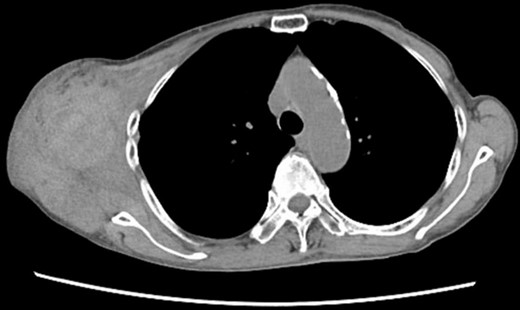

Four days later, the patient was hospitalized for rapidly worsening swelling and pain, and was readmitted with a diagnosis of rebleeding from the chest wall. Physical examination revealed a fist-sized subcutaneous mass on the right side of the chest, with severe pain. Laboratory data indicated anemia (Hb 7.8 g/dl) and no coagulation disorder: % prothrombin time (PT) 115.1%, prothrombin time-international normalized ratio (PT-INR) 0.93, and activated partial thromboplastin time 23.6 s. Computed tomography (CT) at the time of the first hemorrhage showed the hematoma on the right chest and anterior to the scapula (Fig. 2). Contrast-enhanced CT at the time of rebleeding showed an increase in hematoma and extravasation in the peripheral right lateral thoracic artery (Fig. 3). The patient was immediately treated with emergency angiography, which revealed active bleeding from a pseudoaneurysm of the right lateral thoracic artery. Thus, coil embolization was performed (Fig. 4). There were no TAE-related complications and the patient was discharged to home on the fifth hospital day. Oral clopidogrel was resumed and there has been no recurrence of bleeding.

Chest CT at the time of the first bleeding showed formation of a hematoma on the right chest and front of the scapula.